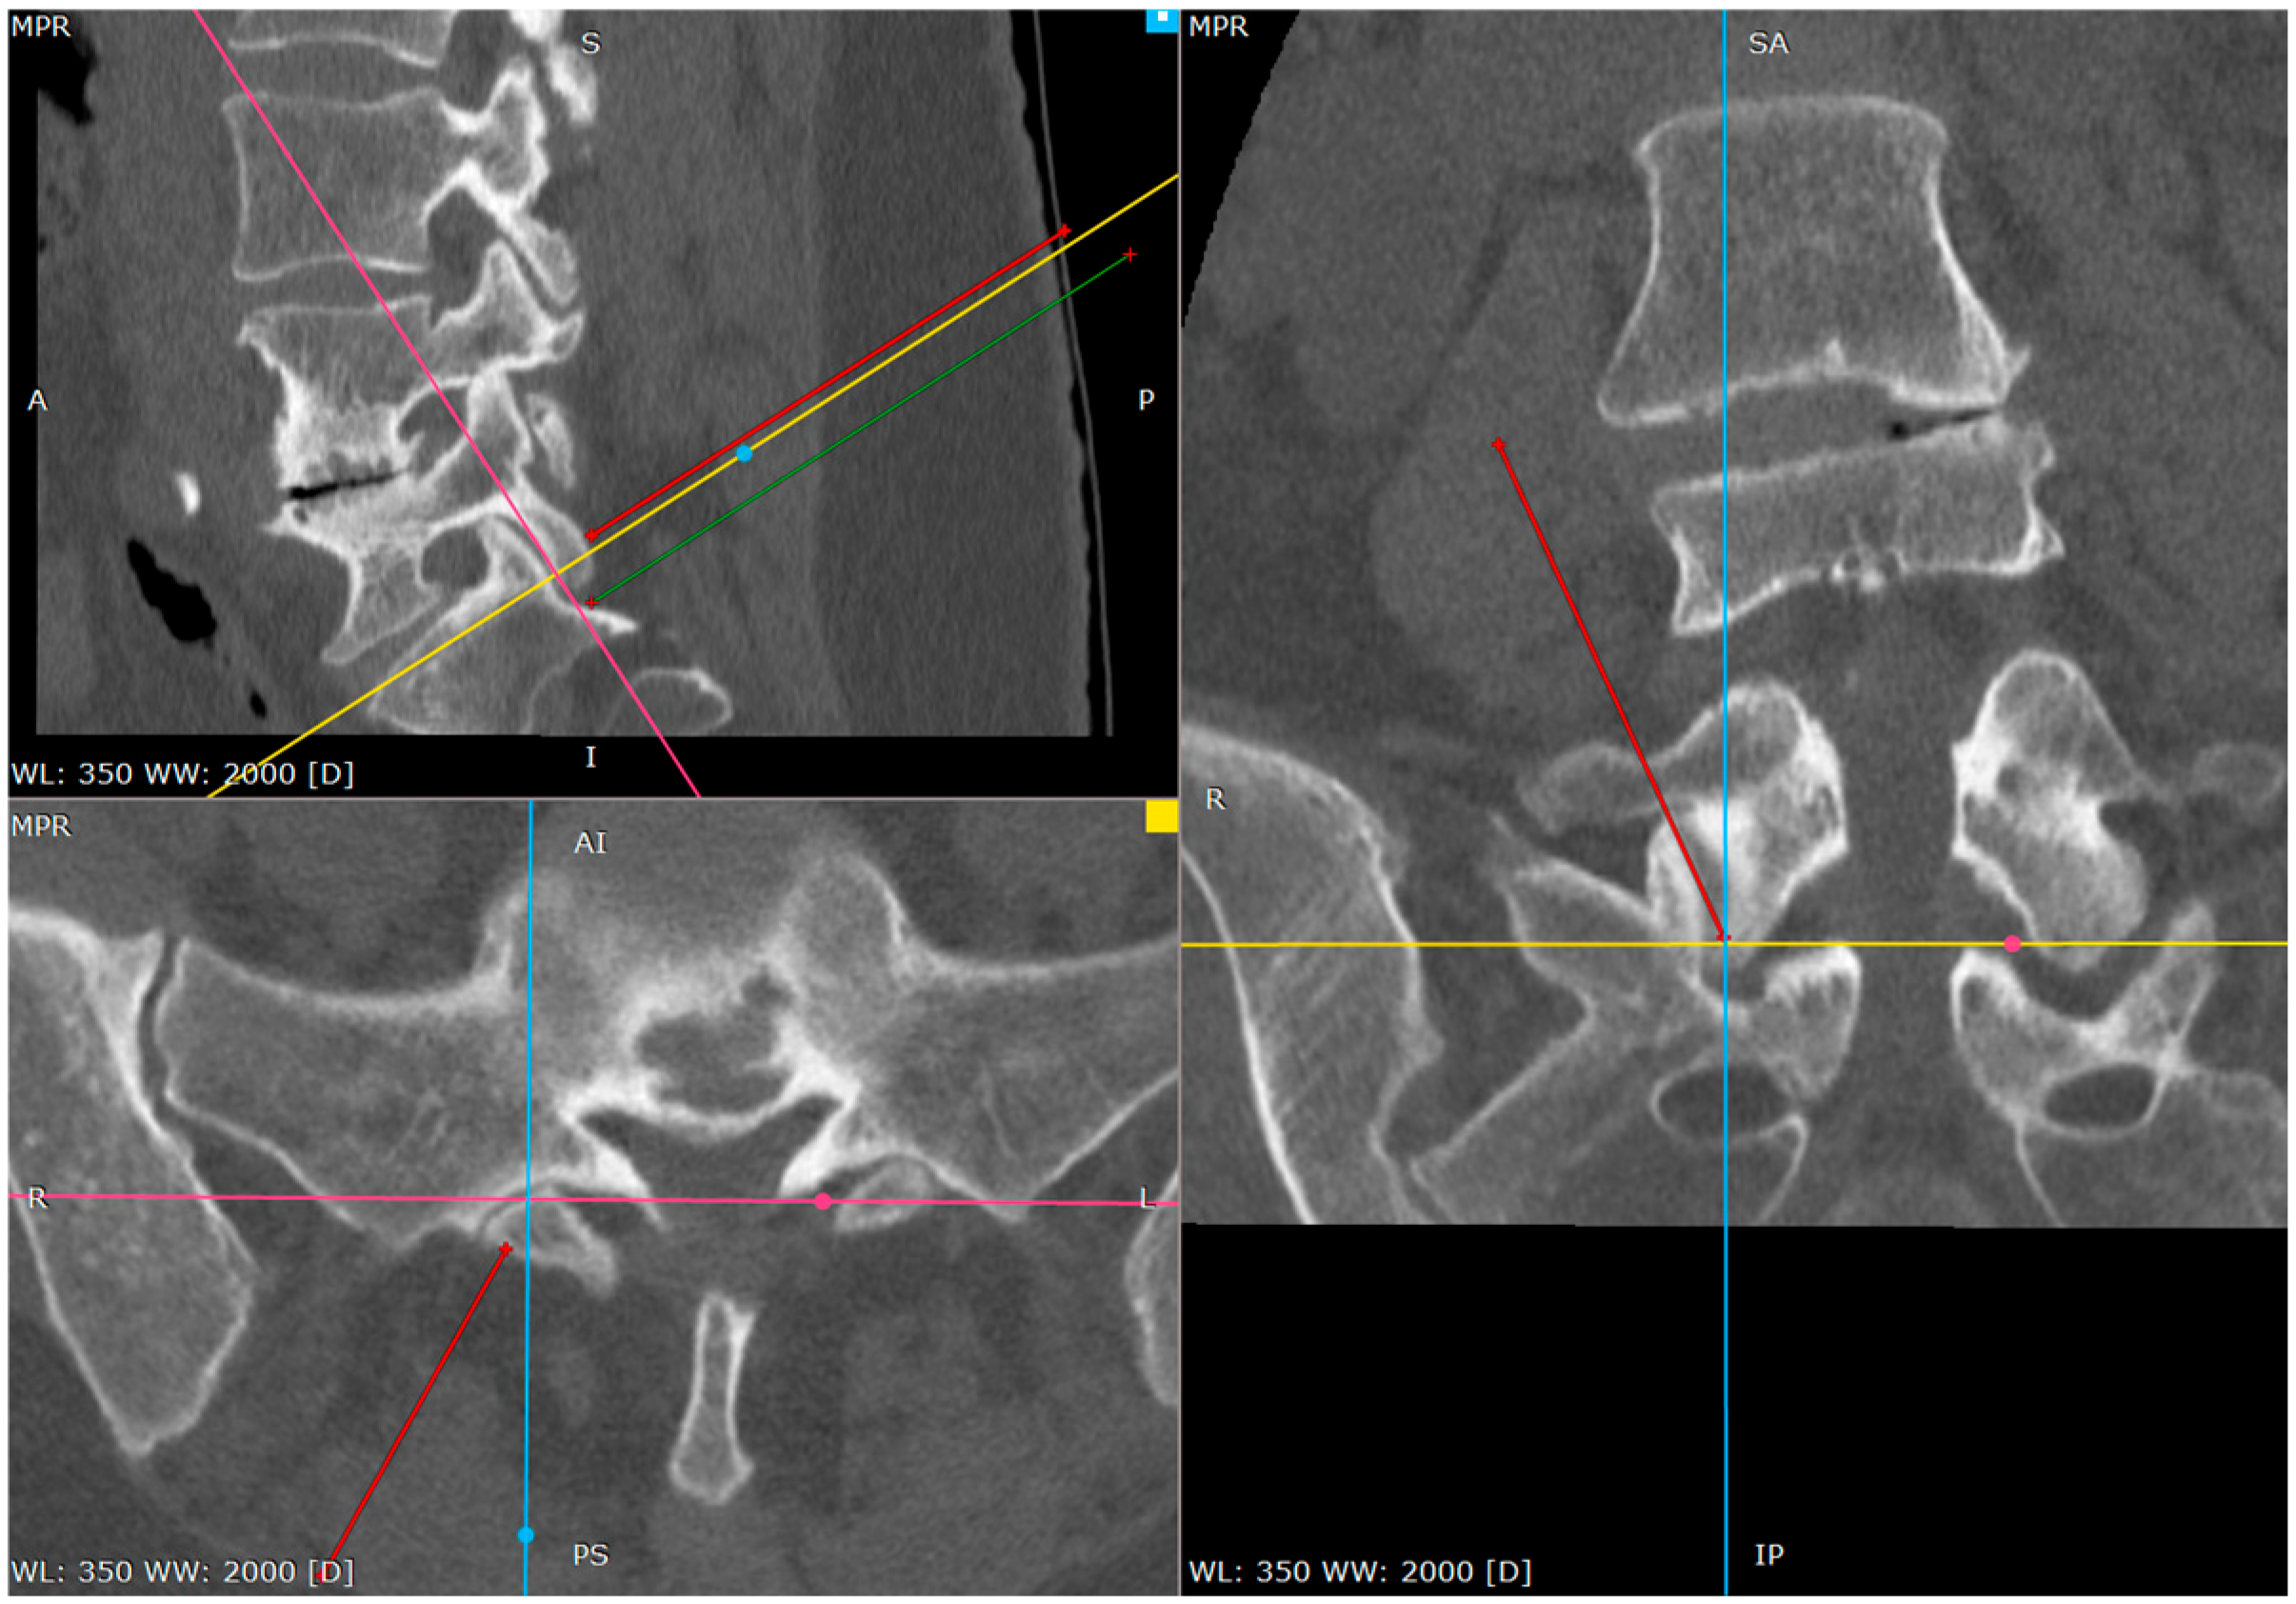

Figure 2. The primary target point—the inferior part of the facet (a CT tri-plane reconstruction).

2.5. Primary Target Point

The primary target point for the needle introduction is the lower part of the facet joint or the caudal part of the articular surface of the S1 superior facet (Figure 2 and Figure 3).

It is safer to aim at the lower part of the facet joint, because it is an easily identifiable structure in any anatomical variation.